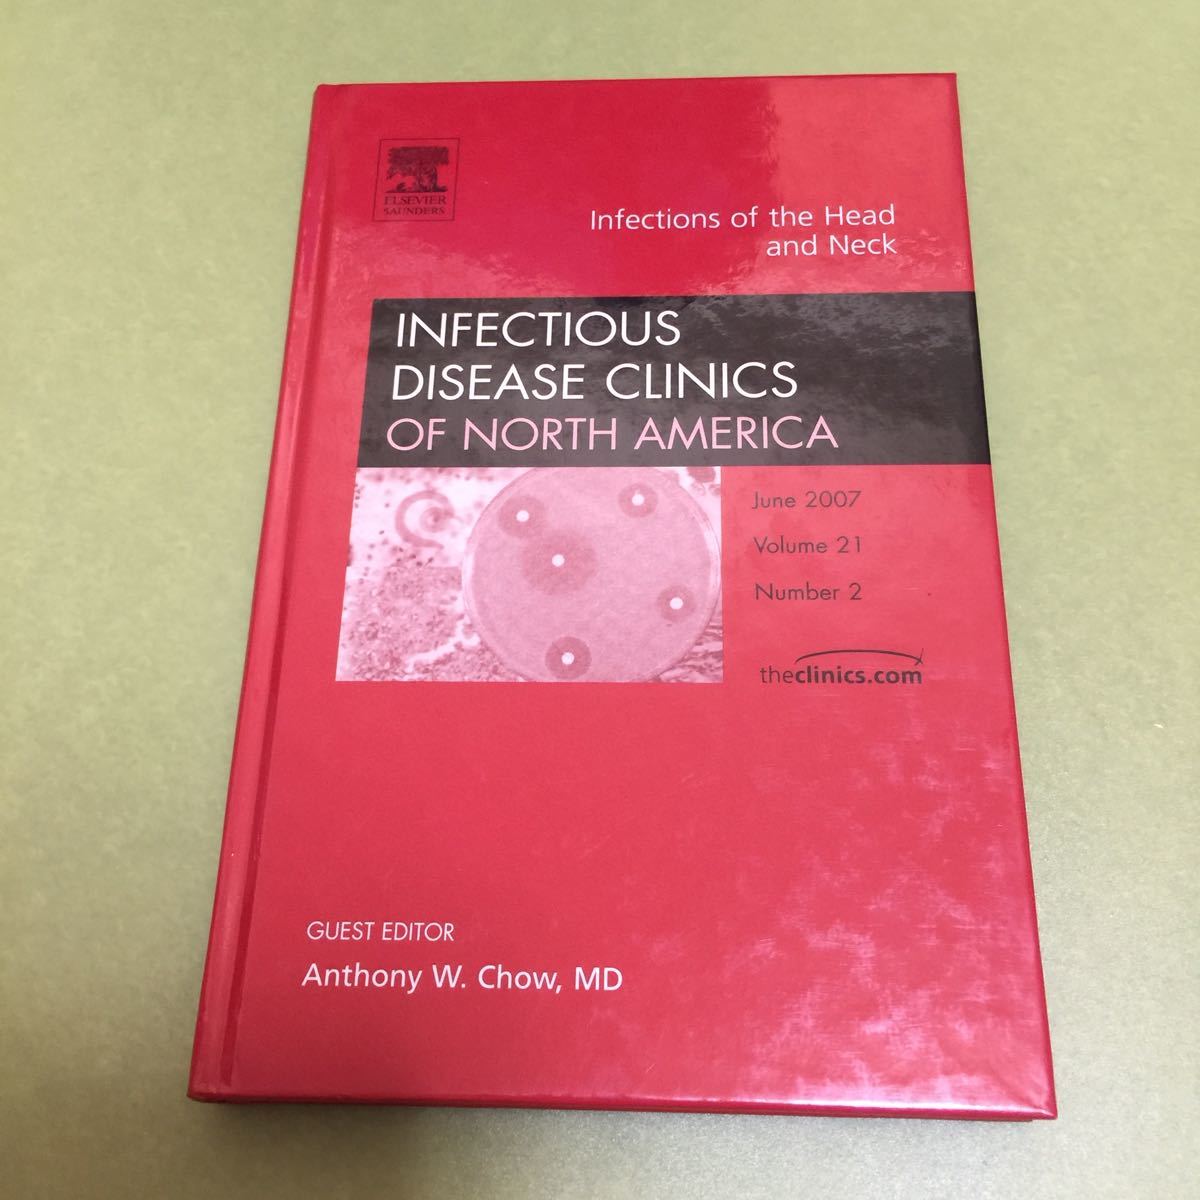

送料無料 通販 A01467950]肺末梢構造にせまる胸部画像診断 - 医学一般 医学一般

商品詳細情報

メーカー | 0c7c0 | 発売日 | 2025-04-12 04:46 | 定価 | 11225円 | ||